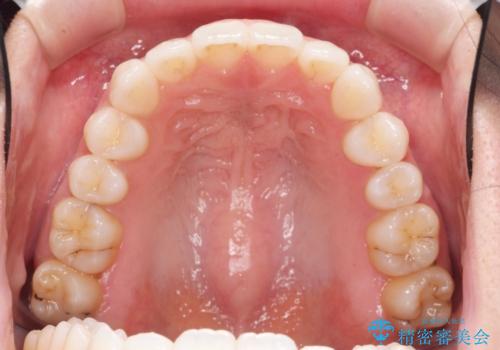

歯を抜かずに後方移動で達成する、前突感の改善

- 前歯が出っ歯のように見えることの改善を求めて来院されました。

当初、セラミックによる治療をご希望されていましたが、相談の結果矯正治療を選択されることとなりました。

通常口元の突出感の改善を行うには小臼歯の4本抜歯が検討されますが、歯のガタ付きが下顎前歯に限定していることから

下顎前歯を1本だけ抜去を行い、上顎の歯は可及的にマイクロインプラントを用いた後方移動を行い口元の印象の改善を計画することとなりました。

マイクロインプラントを用いてしっかりと後方移動を行ったことで前歯の角度は改善され、口元もすっきりと仕上げることができました。